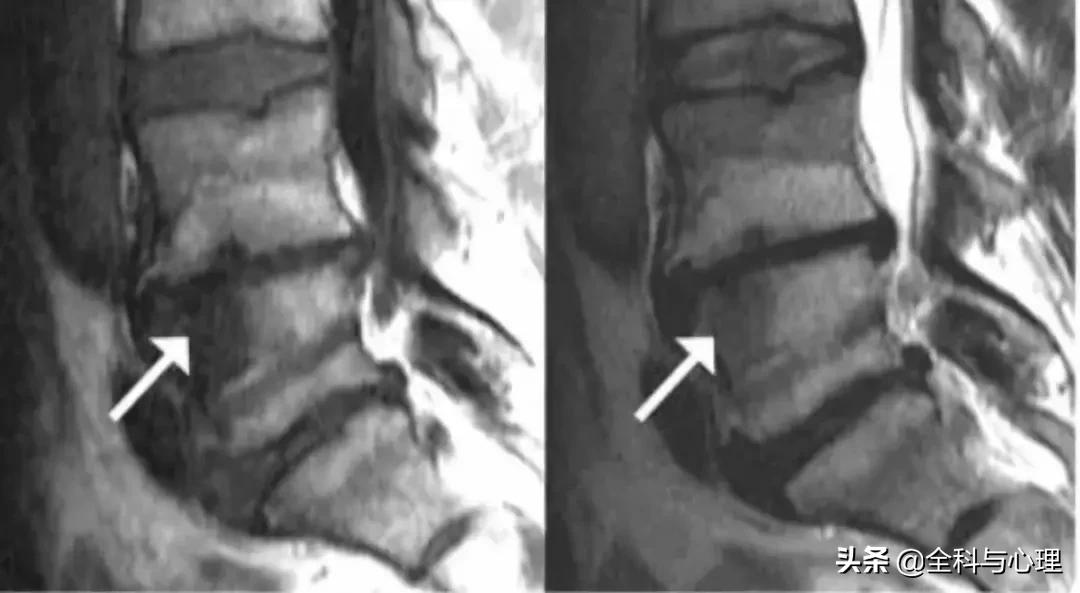

终板源性腰痛在椎间盘造影过程中,造影剂总是流向磁共振显示的终板损伤处,而另一种腰痛的造影过程,造影剂总是通过破裂的纤维环裂隙流向椎间盘的后外侧。

终板破裂分级示意图